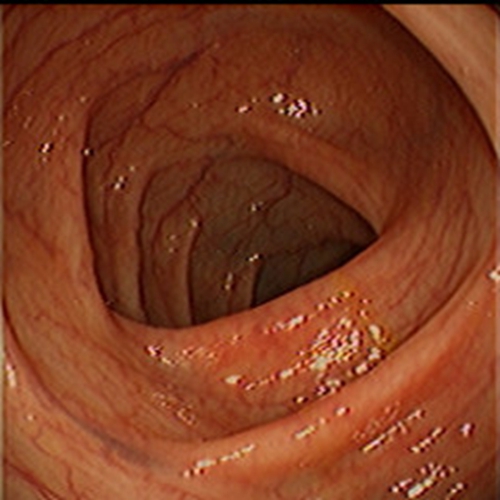

急性胃炎圖片

急性胃炎

急性胃炎胃部